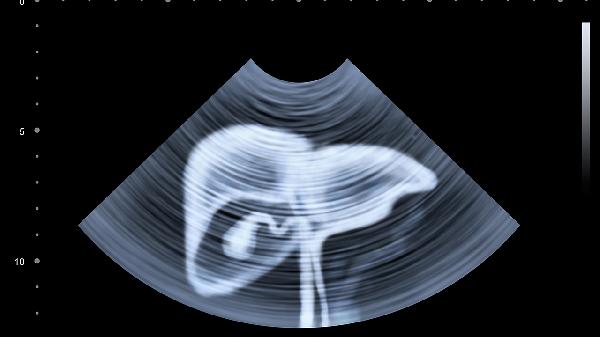

腹肌发育不均衡可能导致左右腹部外观差异,长期单侧发力习惯或运动姿势不当会使一侧腹肌更发达。内脏器官如肝脏位于右上腹,正常体积增大或脂肪浸润可能造成局部隆起。肠道功能紊乱时气体易积聚在升结肠形成右侧腹胀,多与饮食不当或消化吸收不良有关。女性还需考虑右侧卵巢囊肿等妇科问题,肿块生长会推挤腹壁。肝硬化、肝囊肿等疾病引起的肝脏病理性肿大需通过超声检查确诊。

建议每月在相同条件下测量腰围并拍照记录变化,选择宽松衣物减少局部压迫。临床检查需完善血常规、肝功能、肿瘤标志物检测,影像学首选无辐射的超声检查。40岁以上人群出现不明原因腹部不对称时,建议增加胃肠镜检查。孕妇出现右腹偏大需鉴别是否为胎儿体位造成的假性不对称。